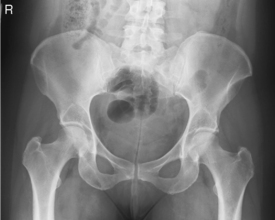

Gonadal shields should be used on pelvis and hip procedures for all male children and adults of childbearing age. Contact shields should be placed over the testes with the upper edge of the shield placed at the inferior margin of the symphysis pubis.

For AP and “frog-leg” laterals of the hips, specially shaped ovarian shields can be carefully placed over the area of the ovaries without obscuring essential anatomy as shown. This should be done on all female children and adults of childbearing age. These ovarian shields, however, may obscure essential anatomy on certain pelvic examinations. Departmental policy regarding shielding and kV range to be used should be determined.

To include proximal femora, pelvic girdle, sacrum, and coccyx

• Supine, pelvis centered to centerline, legs extended

• Both feet, knees, and legs equally rotated internally 15° (secure with tape if necessary). Support under knees for comfort.

• Ensure no rotation of pelvis (ASISs equal distance from TT).

• Center IR to CR. (Include entire pelvis.) Shield gonads (if it doesn’t compromise study).